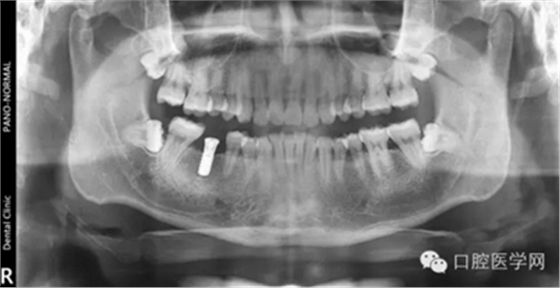

第六种,美国3I种植体

第七种 韩国美格真种植体

第八种,韩国登腾种植体